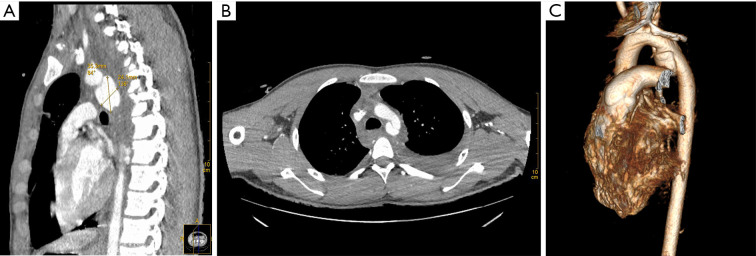

Case description: A 16-year-old male sustained severe multisystem organ injuries after a fall from a five-story building. The patient was critically ill and required intubation during transport. Emergency computed tomography (CT) revealed extensive injuries, including: a descending aorta injury with pseudoaneurysm, bilateral pulmonary contusions with moderate left hemothorax, right pneumothorax, retroperitoneal effusion, right renal contusion with perirenal hematoma, Fractures of the skull base, upper and lower jaw, lumbar spine, sacrum fractures, and severe open wounds in the mouth, right knee joint, and bilateral heels. A multidisciplinary team determined that aortic injury repair should be prioritized. We ultimately performed an unconventional endovascular aortic repair in this adolescent patient. The procedure was completed efficiently without complications, and subsequent interventions successfully addressed the remaining injuries. The patient required a total hospital stay of 733 days and underwent 13 surgical procedures before being successfully discharged following rehabilitation. As of September 2024, the patient remains alive with no complications related to the arterial injury.